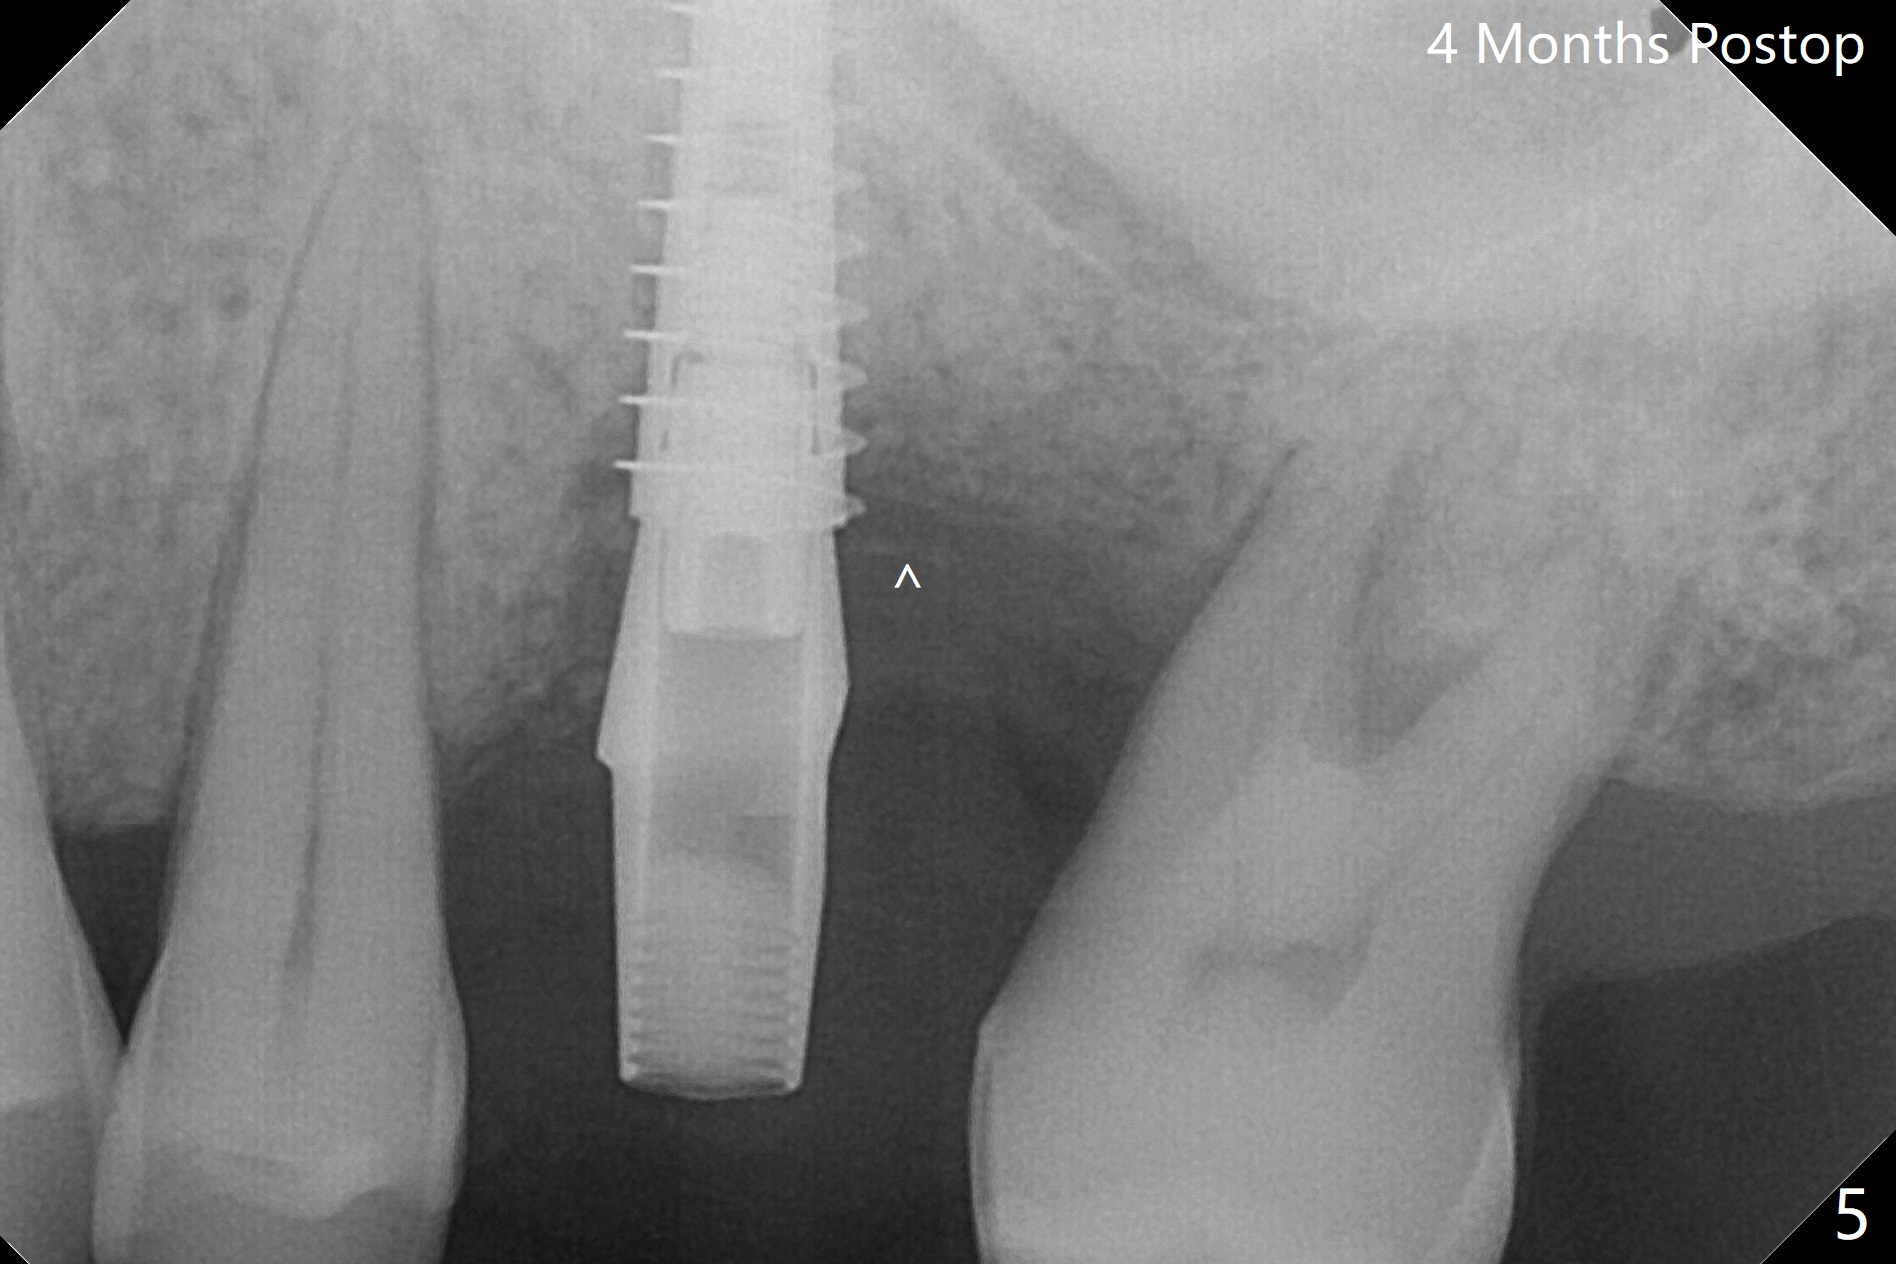

50岁男左上6严重斜型骨质吸收(意味着牙龈特别厚,有可能植入许多骨粉),拔除近中残根后,切开翻瓣,利用导板,4.5x11毫米植体不仅有意近中植入(补偿斜型骨质吸收而造成远中偏移),而且种得表浅(避免使用异常长的基台,改善冠根比例,图一),之后堆入不少粘性骨粉(图二:*),覆盖PRF膜,减张缝合(挺困难),牙周敷料。术后两周,敷料脱落,伤口裂开,但愿骨粉丢失不会太多(图三,四),树脂敷料可能更稳当。术后4个月骨粉好像覆盖远中曾经暴露螺纹(图五:^)。术后四个月伤口愈合(图六),临时牙冠大约3个月。粘固前局部牙龈健康,螺丝扭力30 Ncm。